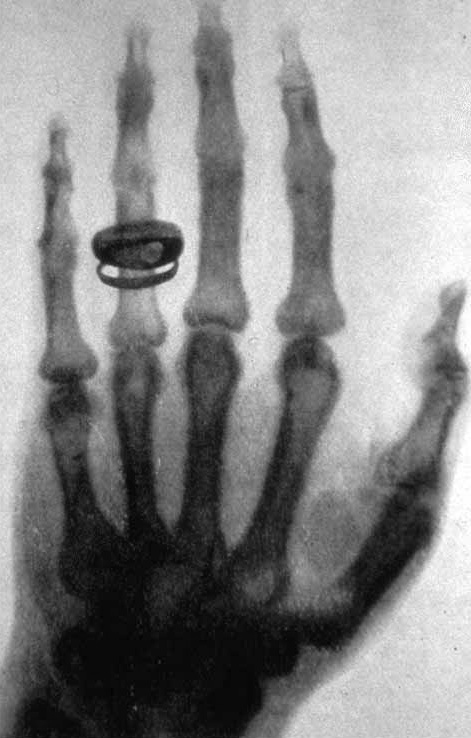

Сделанная В. К. Рентгеном фотография (рентгенограмма) руки Альберта фон Кёлликера

Как оказалось, икс-излучение способно проникать сквозь многие непрозрачные материалы; при этом оно не отражается и не преломляется. Рентгеновское излучение ионизирует окружающий воздух и засвечивает фотопластины. Также Рентгеном были сделаны первые снимки с помощью рентгеновского излучения.